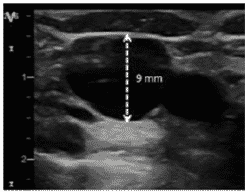

La determinación del calibre es esencial, no solo porque aumenta la probabilidad de punción única exitosa, sino también porque el calibre determinará el tamaño del catéter.

En líneas generales, la mayoría de las guías recomiendan que el catéter no tenga un grosor mayor de 1/3 del diámetro de la vena (1 French equivale a 0.33 mm) para prevenir el riesgo de trombosis.

Para determinar el calibre se empleará el modo 2D y la función “regla”, “diámetro” o su equivalente según le modelo de ecógrafo. Una vez en este modo, el operador se dispondrá a colocar el cursor en la parte superior y medial de la pared de la vena; posteriormente trazará una línea recta hasta llegar al borde opuesto de la pared, obteniéndose, así, el diámetro antero- posterior.